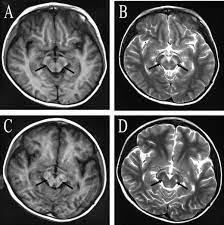

Sau nhiều năm nghiên cứu, các chuyên gia tìm ra căn bệnh khiến nhiều người trở thành "bức tượng sống". Đó là căn bệnh Encephalitis lethargica hay còn gọi là bệnh ngủ.

Theo các chuyên gia, những người mắc căn bệnh Encephalitis lethargica có những triệu chứng ban đầu là buồn ngủ và khó tỉnh dậy như bình thường.

Căn bệnh bí ẩn này lan truyền qua giọt bắn li ti trong không khí. Tuy nhiên, các chuyên gia không thể xác định được nó do loại virus nào gây ra.

Trong khi các nhà khoa học chưa tìm ra lời giải chính xác về nguồn gốc căn bệnh, một giả thuyết cho rằng, căn bệnh Encephalitis lethargica có thể do một chủng vi khuẩn liên cầu hiếm gặp. Đây là loại vi khuẩn gây ra nhiều đợt viêm họng mỗi năm gây ra.

Vi khuẩn trên bị đột biến, tác động đến hệ thống miễn dịch của con người và tấn công não bộ. Điều này khiến người bệnh dần rơi vào tình trạng "đông cứng như tượng".